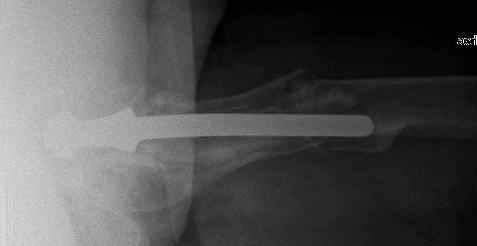

You transformed a cemented hip prosthesis to a cementless revision hip prosthesis with a little approach.

* your nail has a point of minus resistance at the tip of femural stem and at the fulcrum of the fracture; by the time could it break?

* by the time stem and nail could reciprocally move?

* distal fixation of the nail is based near only on two screws : are they sufficient to secure a good stability before fracture consolidation?

The nail tip is jammed. Since it is conical, it can only be jammed more with axial load.

I'd say yes because we use same 6 mm screws for femoral nailing and allow immediate weight-bearing regardless of fracture pattern.